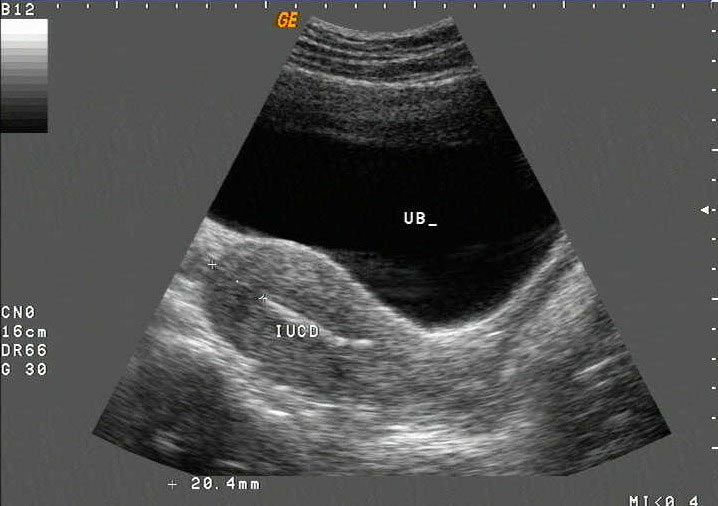

Incorrectly positioned intrauterine devices (IUDs) make intrauterine pregnancy (IUP) more likely, with more than half of IUDs identified during the first trimester of pregnancy malpositioned, according to a study published online Feb. 24 in the American Journal of Obstetrics & Gynecology.

Intrauterine devices (IUDs) can be a safe, effective, and relatively easy birth control option. However, pregnancy can occur if the IUD dislodges or is not placed properly. Dr Elysia Moschos, associate professor of obstetrics and gynecology, and Dr Diane M. Twickler, professor of radiology, at the University of Texas Southwestern Medical Center in Dallas, studied ultrasound findings, clinical symptoms, and outcomes for women with first-trimester pregnancies despite having intrauterine devices to better understand this issue.